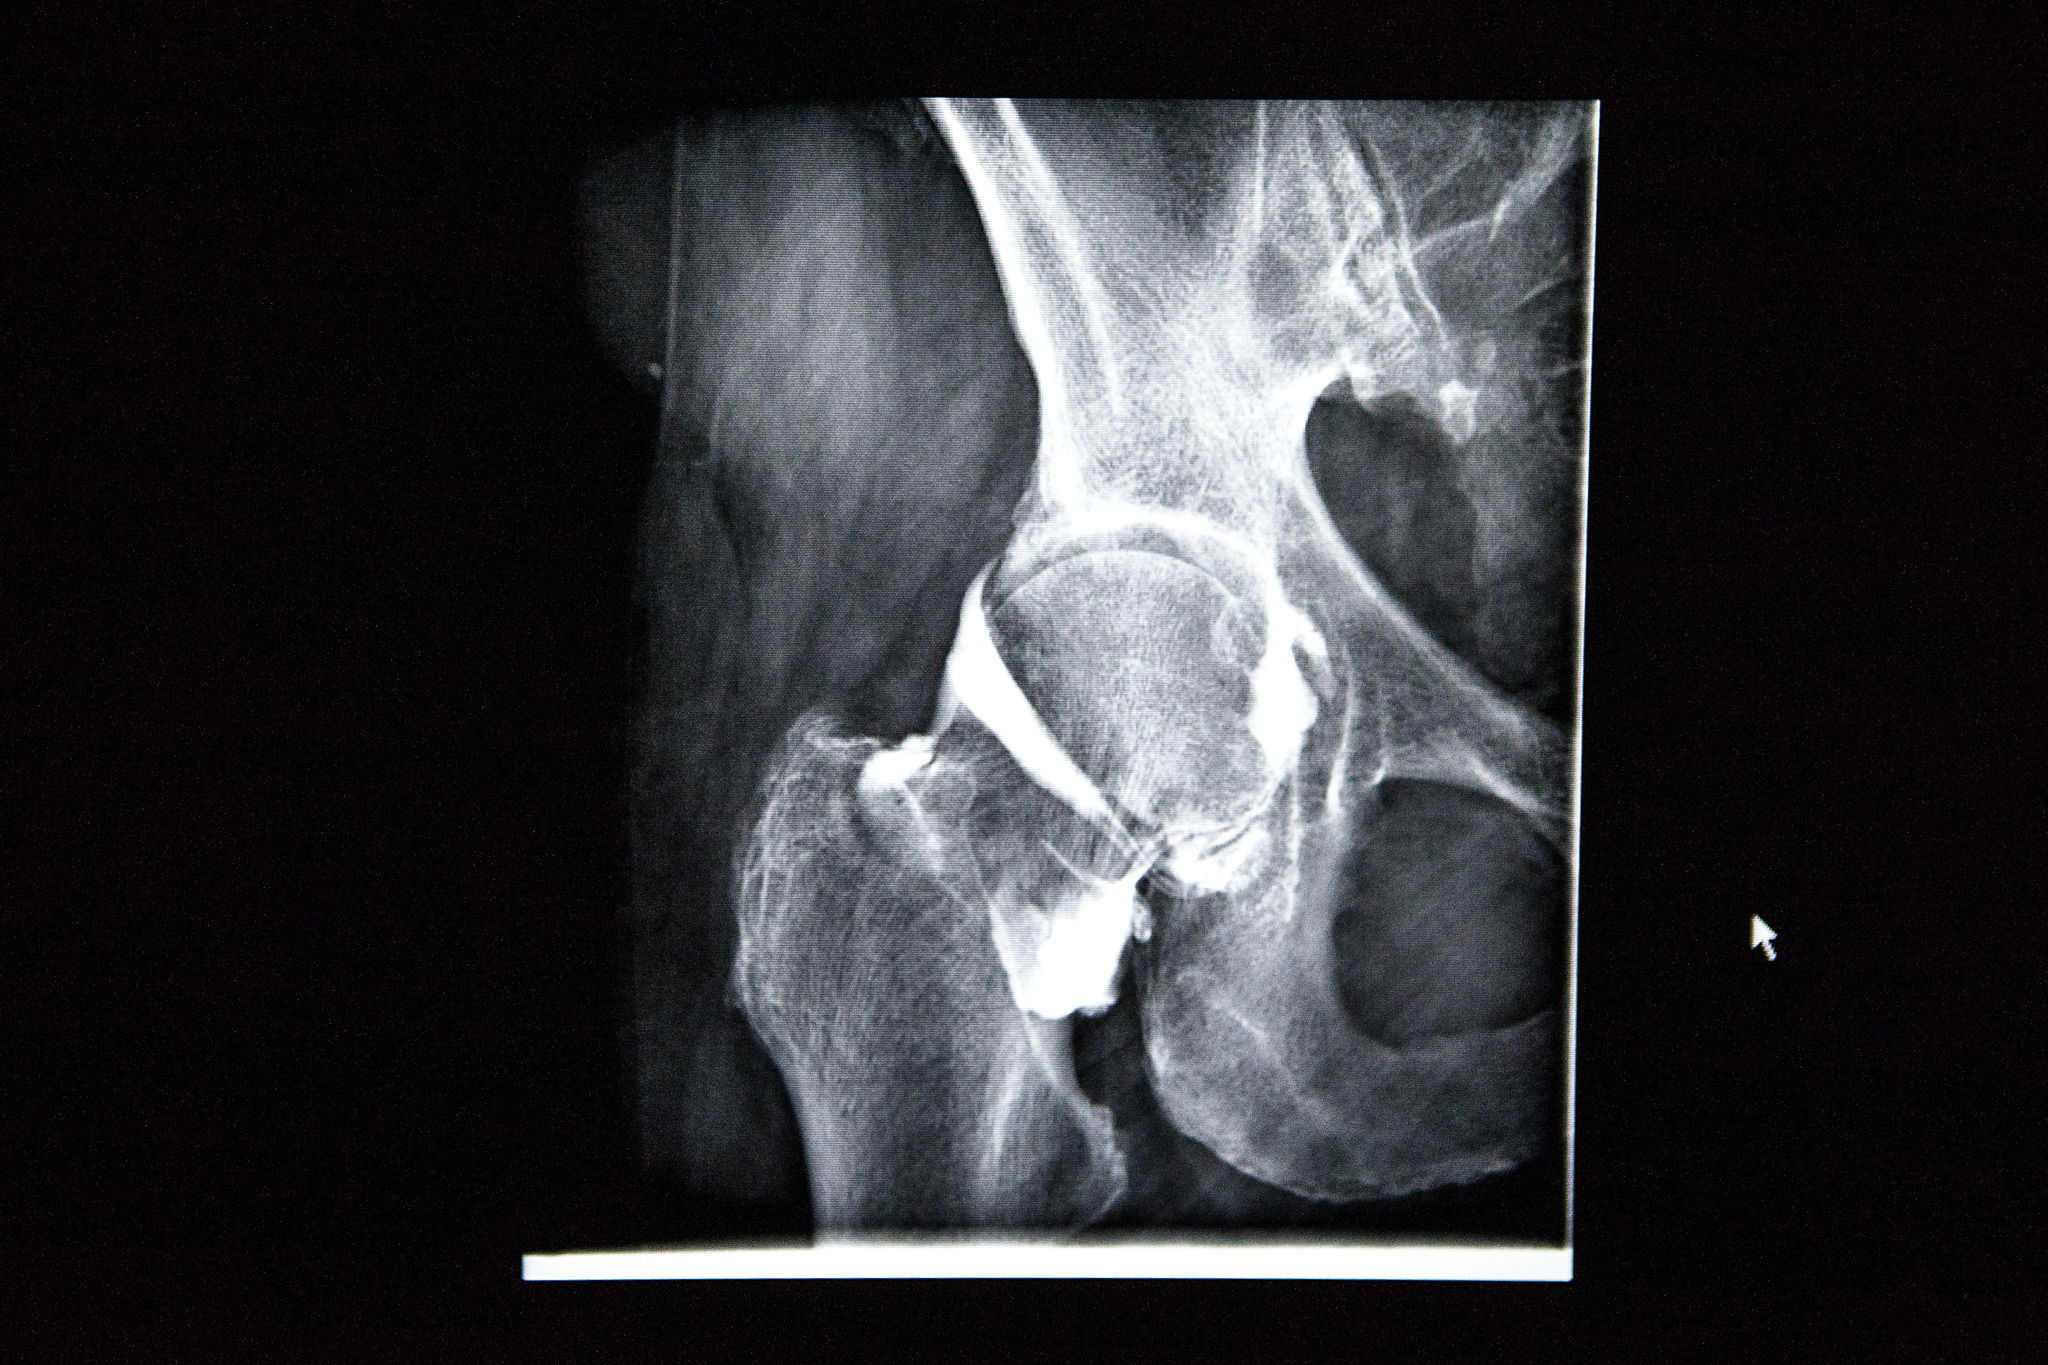

“We started placing thumb prostheses years ago,” says Dr Joris Duerinckx, a surgeon at ZOL. “The thumb joint is replaced by a prosthesis in the form of a miniature ball joint, similar to a hip prosthesis. This offers patients more freedom of movement and comfort than traditional procedures.”